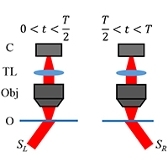

Kowalczuk L., Dornier R., Navarro A., Jeunet F., Moser C., Behar-Cohen F., Mantel I., Adaptive Optics-Transscleral Flood Illumination Imaging of Retinal Pigment Epithelium in Dry Age-Related Macular Degeneration, Cells (2025), 14(9), 633. doi: 10.3390/cells14090633. |

Govindahari V., Dornier R., Ferdowsi S., Moser C., Mantel I., Behar-Cohen F., Kowalczuk L., High-Resolution Adaptive Optics-Trans-scleral Flood Illumination (AO-TFI) Imaging of Retinal Pigment Epithelium (RPE) in Central Serous Chorioretinopathy (CSCR), Scientific Reports, 14.1 (2024):13689. doi: 10.1038/s41598-024-64524-4. |

Kowalczuk L., Dornier R., Kunzi M., Iskandar A., Misutkova Z., Gryczka A., Navarro A., Jeunet F., Mantel I., Behar-Cohen F., Laforest T., Moser C., in vivo Retinal Pigment Epithelium Imaging using Transscleral OPtical Imaging in healthy eyes, Ophthalmology Science, 100234 (2022). |

dos Santos F., Laforest T., Künzi M., Kowalczuk L., Behar-Cohen F., and Moser C., Fully automated detection, segmentation, and analysis of in vivo RPE single cells, Eye, June 2020. |

Laforest T., Künzi M., Kowalczuk L., Carpentras D., Behar-Cohen F. and Moser C. , Transscleral optical phase imaging of the human retina, Nature Photonics, March 2020. |